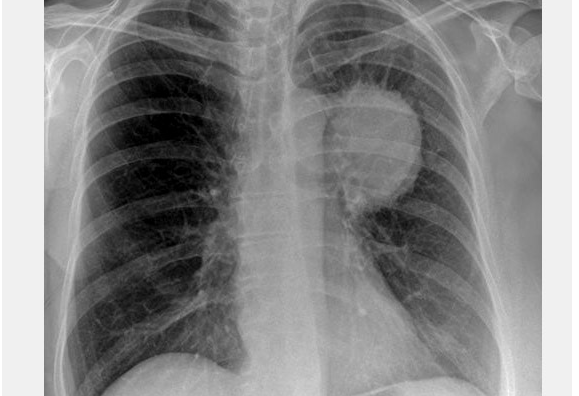

3. eset: Egy férfi, akinek tüdőrákja volt és 1971. március 5-én műtőasztalra került. A műtétre nem került sor, mert az orvosok úgy találták, hogy nagyon szétterjedt a rák és reménytelen a gyógyulás. A férfi április 5-én hallott a spárga kúráról és azonnal elkezdte alkalmazni. Augusztusra a röntgenképen semmi nyoma nem volt a rákos megbetegedésnek.